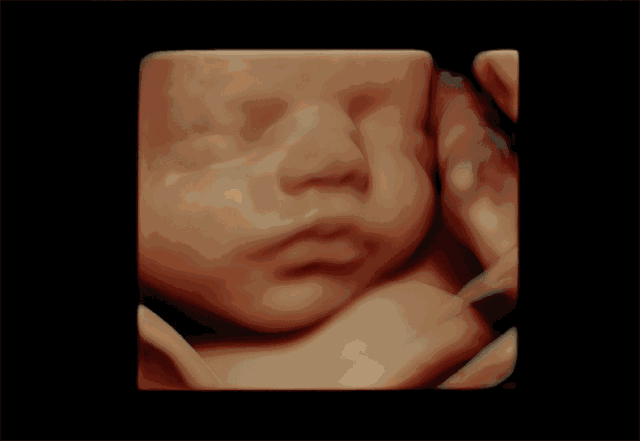

在专业领域上,四维多普勒超声是一种最大化直接了解到腹中婴儿身体状态的一种有效检查方式。

在对孕妇进行四维多普勒超声检查时,医护人员可以检查婴儿发育是否正常,包括器官是否发育正常,脸部特征和头部是否是正常。

观察婴儿手脚和面部发育情况

倘若使用四维多普勒超声检查时,婴儿处于紧握拳头的时刻,两侧长骨可直观了解到,手脚长度正常且齐全,脊柱未扭曲,五官清晰无异常,而且没有兔唇现象

这些现象表明婴儿的手脚以及脸部发育是正常的,没有异常症状,此外,四维多普勒超声还可以测量婴儿的头围和腹围,可以通过检查更多地了解到婴儿的具体情况。